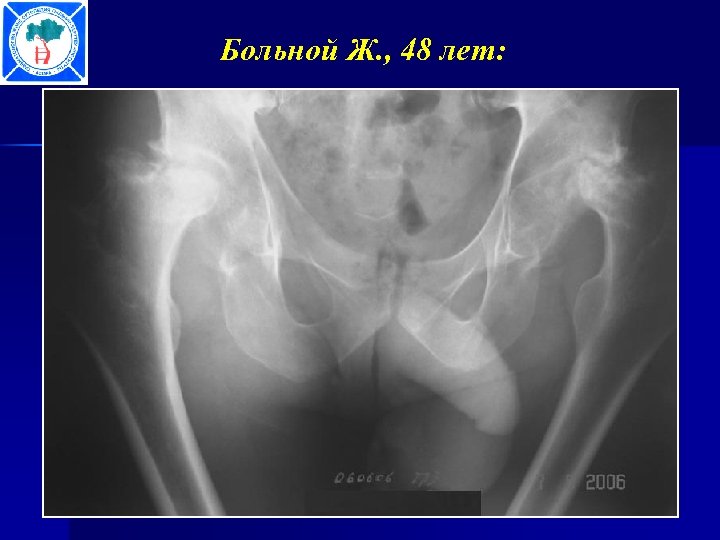

Больной Ж. , 48 лет:

Больной Ж. , 48 лет: Походка через 10 дней после операции